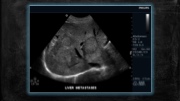

Page 60 - SONO 260 Patologías Hígado - PC2

P. 60